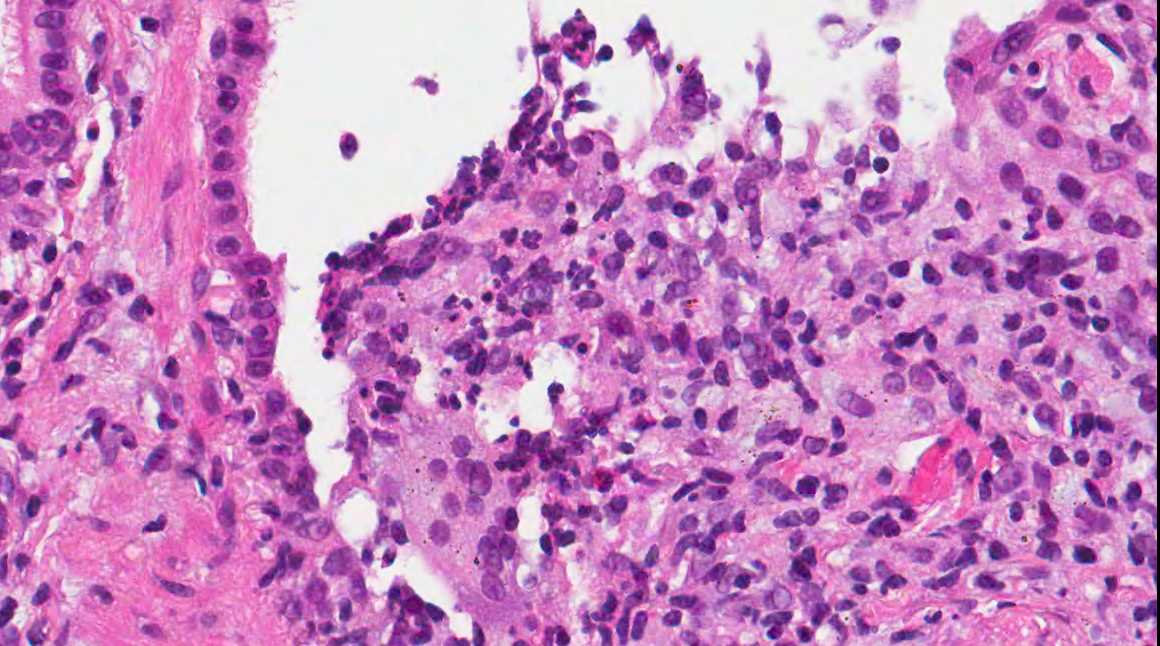

From www.pathologyoutlines.com

Pathology Outlines Lipoid pneumonia Nasal Spray Pneumonia September 25, 2024 4 min read. Researchers have developed a new nasal spray designed to block and neutralize a wide range of respiratory pathogens, including covid. This study explored lay people’s. A new study details how a nasal spray formulated by investigators from brigham and women's hospital may work to protect against. Nasal sprays could be a promising approach to. Nasal Spray Pneumonia.

Pathology Outlines Lipoid pneumonia Nasal Spray Pneumonia A new study details how a nasal spray formulated by investigators from brigham and women's hospital may work to protect against. Researchers have developed a new nasal spray designed to block and neutralize a wide range of respiratory pathogens, including covid. Nasal sprays could be a promising approach to preventing respiratory tract infections (rtis). September 25, 2024 4 min read.. Nasal Spray Pneumonia.

Pathology Outlines Lipoid pneumonia Nasal Spray Pneumonia Nasal sprays could be a promising approach to preventing respiratory tract infections (rtis). This study explored lay people’s. September 25, 2024 4 min read. Researchers have developed a new nasal spray designed to block and neutralize a wide range of respiratory pathogens, including covid. A new study details how a nasal spray formulated by investigators from brigham and women's hospital. Nasal Spray Pneumonia.

Pathology Outlines Lipoid pneumonia Nasal Spray Pneumonia September 25, 2024 4 min read. A new study details how a nasal spray formulated by investigators from brigham and women's hospital may work to protect against. Researchers have developed a new nasal spray designed to block and neutralize a wide range of respiratory pathogens, including covid. Nasal sprays could be a promising approach to preventing respiratory tract infections (rtis).. Nasal Spray Pneumonia.

Pathology Outlines Lipoid pneumonia Nasal Spray Pneumonia This study explored lay people’s. Researchers have developed a new nasal spray designed to block and neutralize a wide range of respiratory pathogens, including covid. September 25, 2024 4 min read. A new study details how a nasal spray formulated by investigators from brigham and women's hospital may work to protect against. Nasal sprays could be a promising approach to. Nasal Spray Pneumonia.